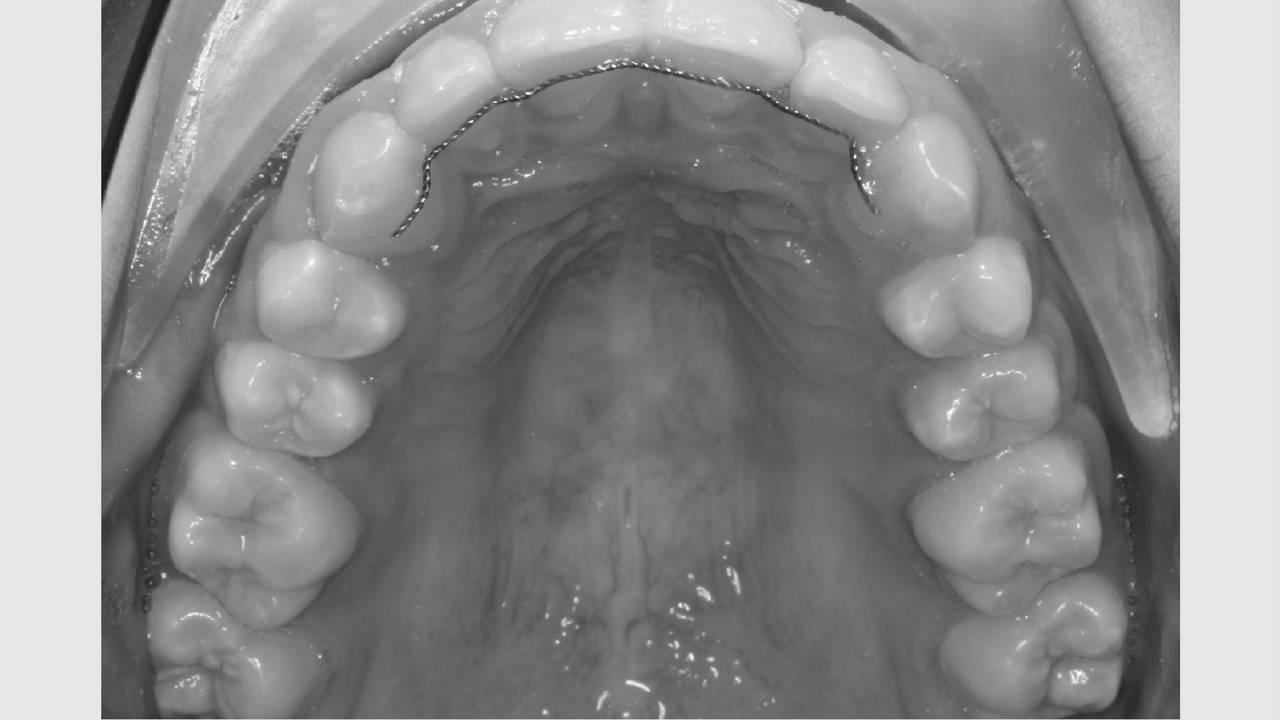

Faste bøjler - "togskinner"

Ofte er der brug for fastsiddende bøjler på tænderne. Mange kalder dem "togskinner", hvilket er et passende navn, da tænderne nærmest bliver flyttet i et spor på den lås, der limes på tanden.

For at plasten kan hærde, lyses der på tanden med ultraviolet lys i 20 sekunder. For at beskytte vores øjne mod det ultraviolette lys, bliver der holdt en orange skærm for øjnene. Når alle låse er limet på, forbindes de med en bue af metal. Det er den, der flytter på tænderne.

Det tager i gennemsnit 2 år at få rettet tænder med fast bøjle, hvorefter du får nogle holdebøjler. Der limes ofte en tråd bag på fortænderne i over- og underkæbe. Derudover får du en skinne eller plade til at sove med hver nat i omkring to år efter, bøjlen er taget af. Disse holdebøjler er vigtige at bruge og holde ved lige, hvis man ønsker at bevare tænderne i deres nye position.